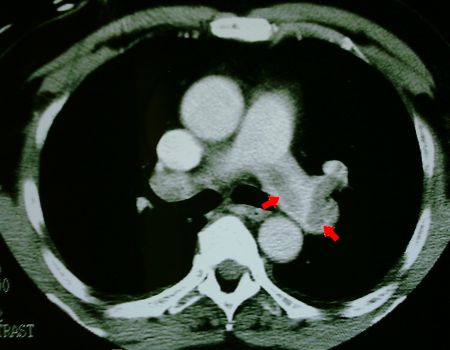

CT of pulmonary artery showing large thrombus extending into right

pulmonary artery

Fig 2. CT showing long thrombus extending into right pulmonary artery.